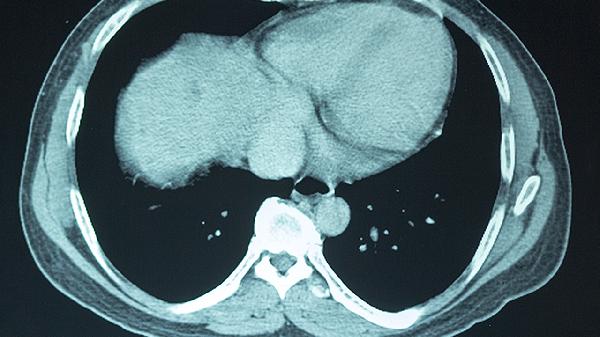

脑震荡后遗症可能包括头痛、头晕、注意力不集中、记忆力减退、睡眠障碍等症状。脑震荡通常由头部受到外力冲击引起,可能导致脑功能暂时性障碍。若出现上述症状,建议及时就医,通过神经影像学检查评估脑部损伤程度,并遵医嘱进行康复治疗。

脑震荡后恢复期间应保持适度休息,避免过早恢复剧烈运动或高强度脑力劳动。饮食上可增加富含欧米伽3脂肪酸的深海鱼、坚果等食物,补充B族维生素促进神经修复。若症状持续超过1个月或加重,需及时复查头颅CT或MRI排除其他颅内病变。康复训练需在专业医师指导下循序渐进进行,避免自行使用未经证实的偏方或保健品。